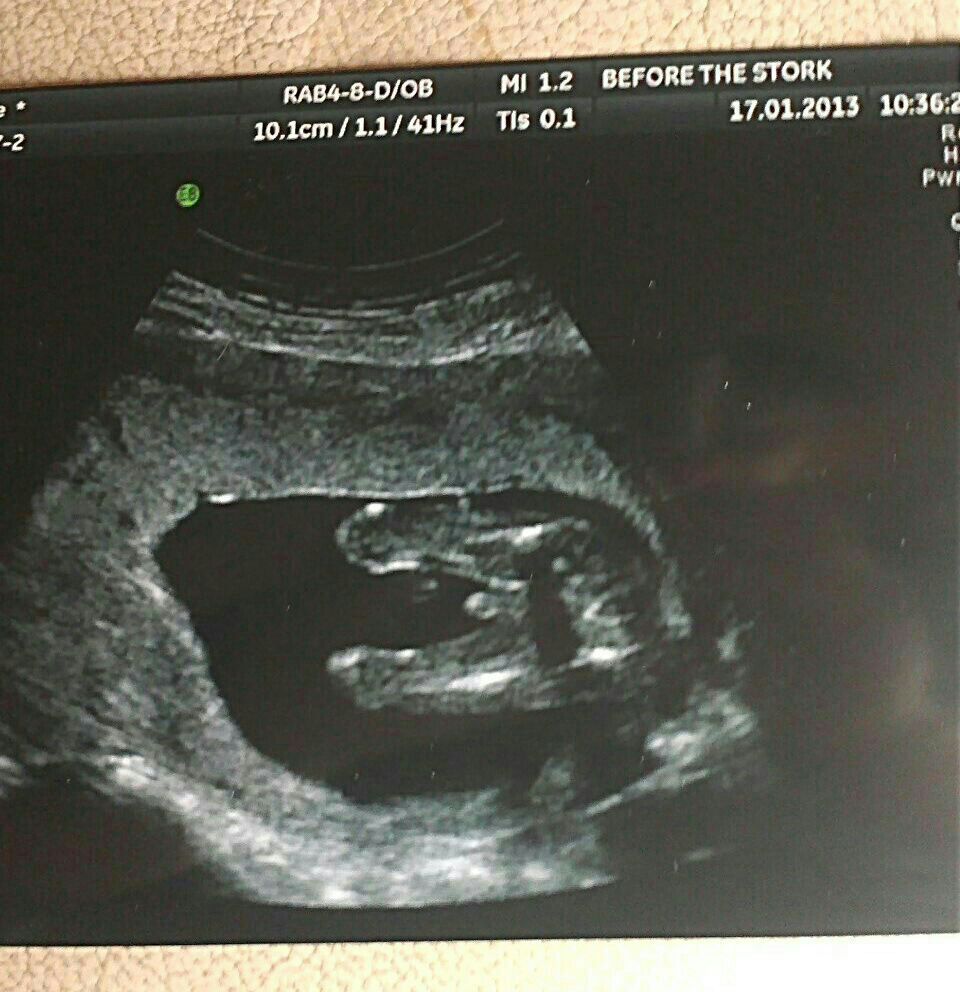

hi guys prob gonna ask a complete silly question now, but im not 100% convinced by my potty shot of my little boy. ive been comparing it to others and i just don't think it looks the same as any of their boys bits, it seems obvious that something sticking out this big must be a little boy but were are his testicles and it doesn't much look turtle like, any ideas why it seems different, or is it just me ha. thanks for having a look xx

Attachment 8327